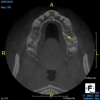

(4.) In a CBCT image axial view, the MB1 and MB2 canals are readily visible in tooth No. 14, and in the coronal view, these two separate canals can be seen to merge into a single apical opening.

Figure 4

(5.) In a CBCT image axial view, the MB1 and MB2 canals are readily visible in tooth No. 14, and in the coronal view, these two separate canals can be seen to merge into a single apical opening.

Figure 5